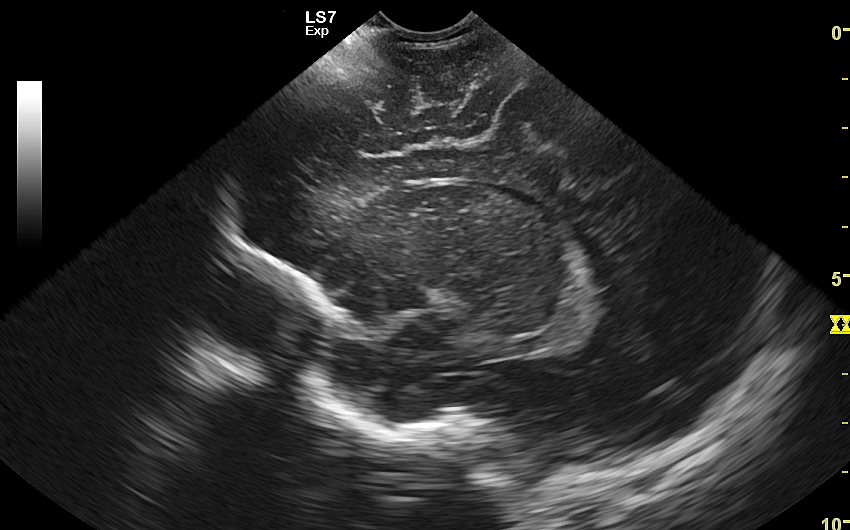

USG główki to podstawowa metoda diagnostyczna mózgu i struktur okołomózgowych u wcześniaków, noworodków i niemowląt. Badanie jest bezbolesne i nieryzykowne w porównaniu do rezonansu magnetycznego, podczas którego dziecko poddawane jest znieczuleniu ogólnemu. Przeprowadzenie szerokiego i szczegółowego badania USG główki jest możliwe aż do momentu zarośnięcia ciemiączka, czyli chrzęstnej struktury w pokrywie czaszki. Ze względu na cienką kość skroniową czaszki dziecka w późniejszym okresie możliwa jest wciąż częściowa ocena mózgowia w badaniu USG. Ambulatoryjne badanie USG przezciemiączkowe zwykle zalecane jest przez neonatologa, pediatrę lub neurologa dziecięcego w celu oceny mózgu wcześniaków, dzieci z małą masą urodzeniową, dzieci po epizodzie niedotlenienia lub krwawienia wewnątrzczaszkowego w trakcie porodu lub okresu noworodkowego, a także w przypadku wystąpienia drgawek, podejrzenia wady układu nerwowego, np. wodogłowia.

Badania USG mózgu dziecka wykonywane w warunkach szpitalnych i ambulatoryjnych różnią się od siebie charakterem stwierdzanych patologii. W szpitalu dominują ostre krwawienia wewnątrzczaszkowe oraz śródmózgowe. Z kolei najczęstszymi chorobami i stanami patologicznymi, które spotyka się w trakcie badania USG przezciemiączkowego przeprowadzanego w warunkach ambulatoryjnych są pozostałości po krwawieniach dokomorowych oraz śródmózgowych w postaci poszerzenia układu komorowego i torbieli; pozostałości po uszkodzeniach niedokrwiennych w postaci leukomalacji okołokomorowej i zaników mózgowych; poza tym zmiany pozapalne i wodogłowie wewnętrzne bądź zewnętrzne. Sporadycznie wykrywane są wady rozwojowe oraz guzy mózgu.

Badanie USG służy również ocenie dojrzałości mózgowia dziecka; otóż mózg wcześniaka różni się od mózgu starszego niemowlęcia. U tego pierwszego obserwuje się m. in. mniej zaawansowane bruzdowanie kory mózgowej oraz warianty rozwojowe, z których najczęstszym jest jama przegrody przezroczystej. Zaburzenia rozwoju kory mózgowej u płodu, a potem u niemowlęcia, obserwowane są w przypadku palenia papierosów przez ciężarną lub spożywania przez nią alkoholu, w przypadku powikłań przebiegu ciąży, a także powikłań okołoporodowych.